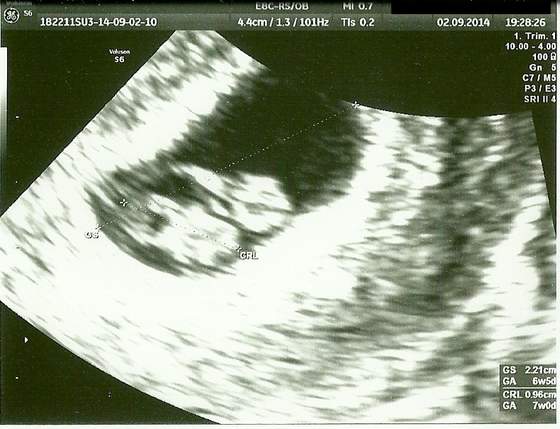

Nie jestem juz fasolka, ale małym człowieczkiem, mam mini nosek, nozki i ramionka. Mierze 22mm. Serducho bije jak dzwon! Byłem bardzo ruchliwy i pokazałem sie ze wszystkich stron, to białe nade mną to pępowina ;D